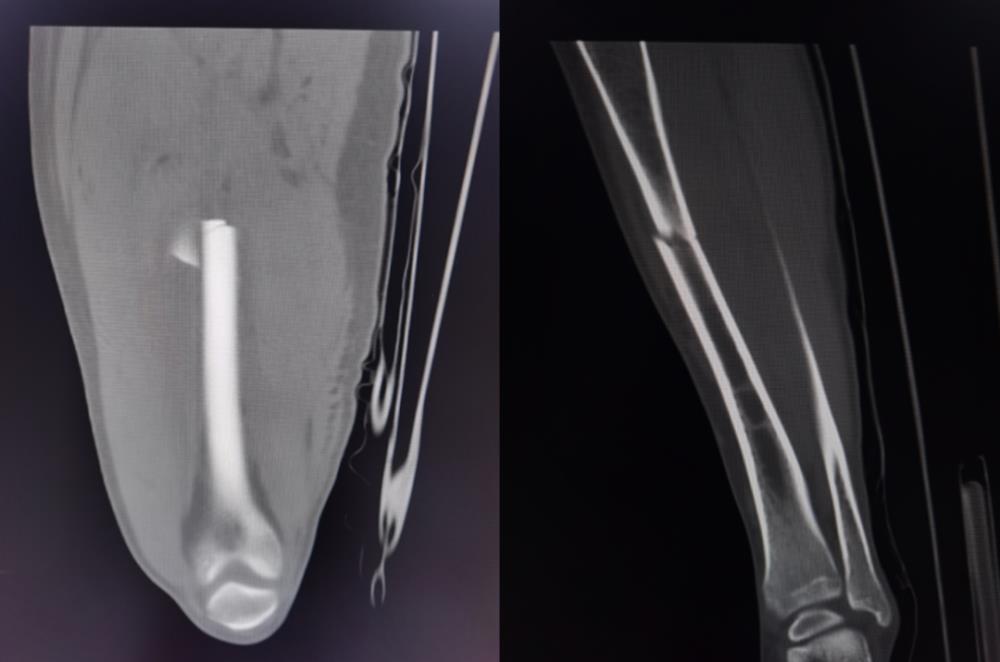

近日,我院收住了一名15岁因车祸骨折入院的患者,CT提示为右股骨干骨折、右胫骨上段骨折,本身这类患者在我院非常常见,但是他却出现了罕见的中风情况,情况非常凶险。

患者经ICU积极治疗后,在住院第4天完全清醒,言语流利,对答切题,肢体活动良好。由于病情危重,暂时无法行手术治疗,入院后行骨牵引固定,减轻骨折处疼痛。于住院第6天顺利转出普通病房。住院第11天,复查颅脑CT提示梗死病灶完全消失。病情稳定后于住院第17天行手术治疗,住院第31天顺利出院。